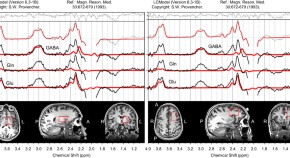

Using fMRI and MRS measurements from healthy, young adults, Dolfen et al examined the effects of motor learning and stress on striatal and hippocampal GABA levels, as well as effects on neural correlates of learning. They demonstrated that stress modulated the link between striatal GABA levels and functional plasticity in the hippocampus and striatum, which reveals a role for GABA in the stress-induced modulation of these systems.